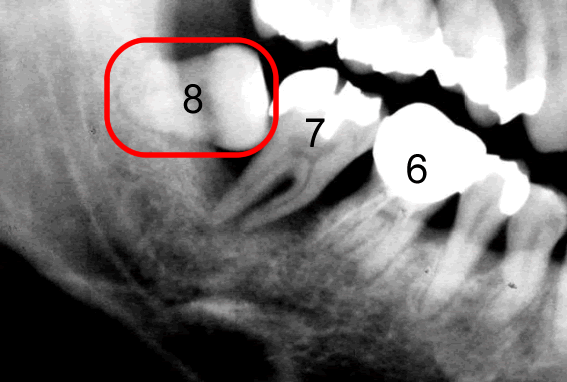

このレントゲン写真は40代の方です。

8番目が親知らずです。

横に向いて生えていますね。

親知らずの手前の歯7番目、その手前の歯6番目、どうなっているでしょう?

6番目は斜めに倒れて、かつ、上に上がっていますね。

親知らずに押し上げられているんですね。

このレントゲン写真でもう一つ重要なことが、あります。

それは、親知らずのすぐ手前の7番目の歯の根っこをご覧下さい。

歯を支えている骨が溶けているんです。

レントゲン写真というのは硬いところが白くうつります。

5番目の歯の根っこのあたりは歯の根の周りがまだもや~っと白くうつっています。

これは「骨」が写っているんです。

しかし、7番目には、骨が、ない。

さらに6番目の根っこの7番目よりのあたりまで骨が溶けています。

7番目の歯を支えている骨が全然ないのです。

6番目の歯を支えている骨が後ろ半分ないのです。

ということはこの7番目の歯はグラグラに揺れています。

抜かなければならないということです。

ほっといてもそのうち勝手に抜けます。

「親知らず」を抜かずに放置しておいたために、その「親知らず」が横に押し上に押し、さらにこの7番と8番の間に溜まったバイ菌が取りきれないわけです。